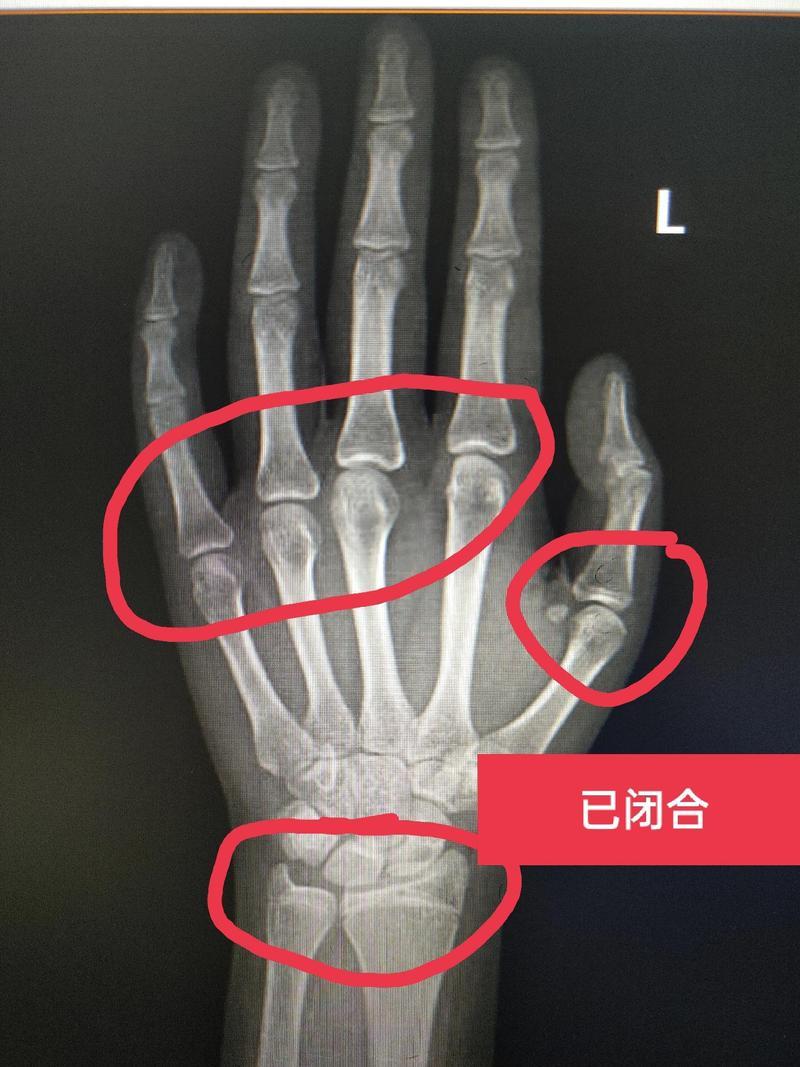

媽媽這時才懂得着急了,趕緊帶着琪琪去看醫生,而醫生做了一系列檢查之後發現孩子的骨骼已經閉合了。

正常情況下,孩子要到14歲甚至15歲骨骼纔開始閉合,而琪琪才11歲骨骼就閉合了,身高就基本定型在1米46了,最多也只能長個2~3釐米,也就是達不到1米5了。